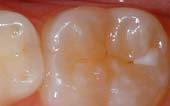

Before Sealant Applied

After Sealant Applied